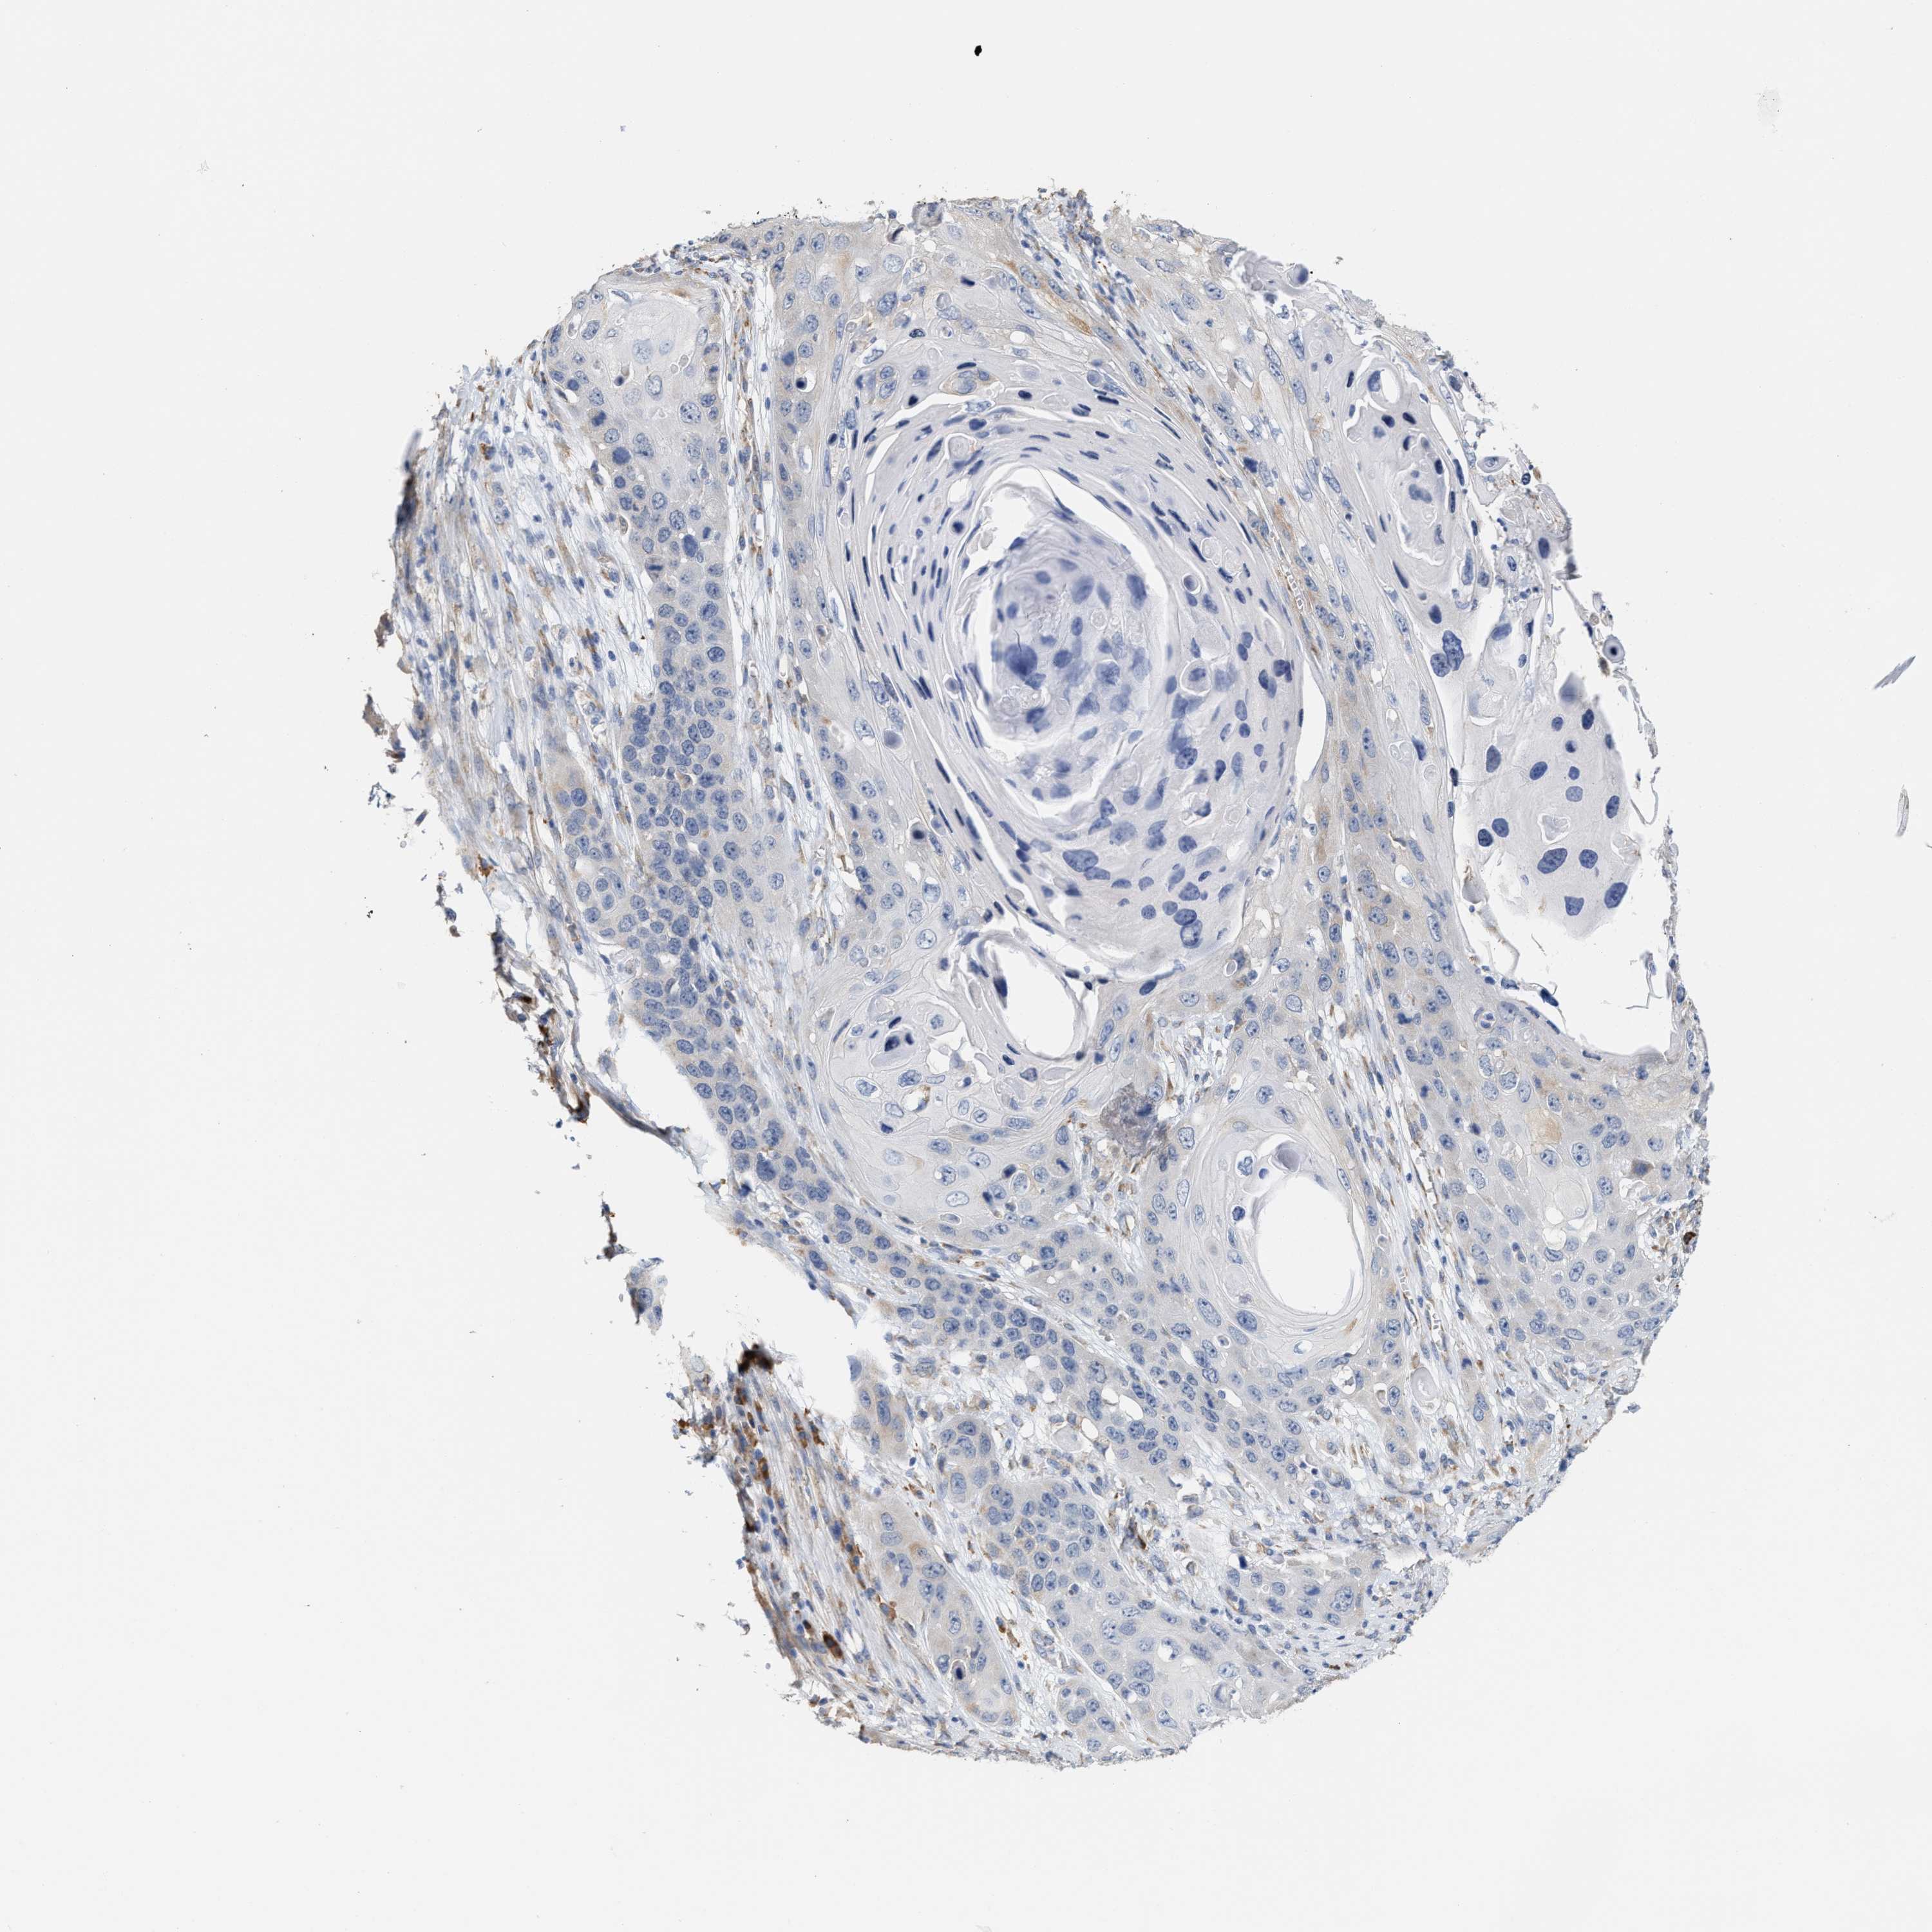

Basal cell and squamous cell cancer

SKIN CANCER - Protein expressioni

A mouse-over function shows sample information and annotation data. Click on an image to view it in a full screen mode. Samples can be filtered based on level of antibody staining by selecting one or several of the following categories: high, medium, low and not detected. The assay and annotation is described here.

Antibody stainingi

Antibody staining in the annotated cell types in the current human tissue is reported as not detected, low, medium, or high, based on conventional immunohistochemistry profiling in selected tissues. This score is based on the combination of the staining intensity and fraction of stained cells.

Each image is clickable and will lead to virtual microscopy that enables deeper exploration of all samples and also displays staining intensity scores, fraction scores and subcellular localization as well as patient and tissue information for each sample.

Antibody HPA020028

Staining

High

Medium

Low

Not detected

Intensity

Strong

Moderate

Weak

Negative

Quantity

>75%

75%-25%

<25%

None

Location

Nuclear

Cytoplasmic/membranous

Cytoplasmic/membranous,nuclear

Basal cell carcinoma

Squamous cell carcinoma, NOS

Squamous cell carcinoma, metastatic, NOS